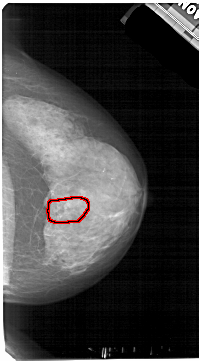

A_1605_1.LEFT_CC

FILE: A_1605_1.LEFT_CC.OVERLAY

TOTAL_ABNORMALITIES 1

ABNORMALITY 1

LESION_TYPE CALCIFICATION TYPE PLEOMORPHIC DISTRIBUTION SEGMENTAL

ASSESSMENT 4

SUBTLETY 3

PATHOLOGY BENIGN

TOTAL_OUTLINES 1

BOUNDARY